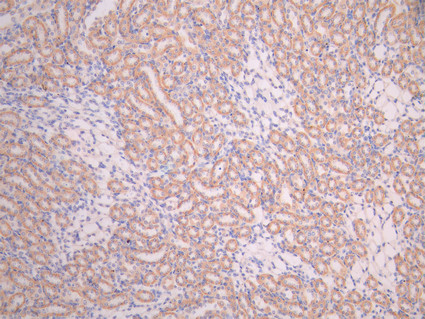

IHC image of CSB-RA007743MA1HU diluted at 1:50 and staining in paraffin-embedded human kidney tissue performed on a Leica BondTM system. After dewaxing and hydration, antigen retrieval was mediated by high pressure in a citrate buffer (pH 6.0). Section was blocked with 10% normal goat serum 30min at RT. Then primary antibody (1% BSA) was incubated at 4°C overnight. The primary is detected by a Anti-Human lgG, Fcy Fragment Specific labeled by HRP and visualized using 0.05% DAB.